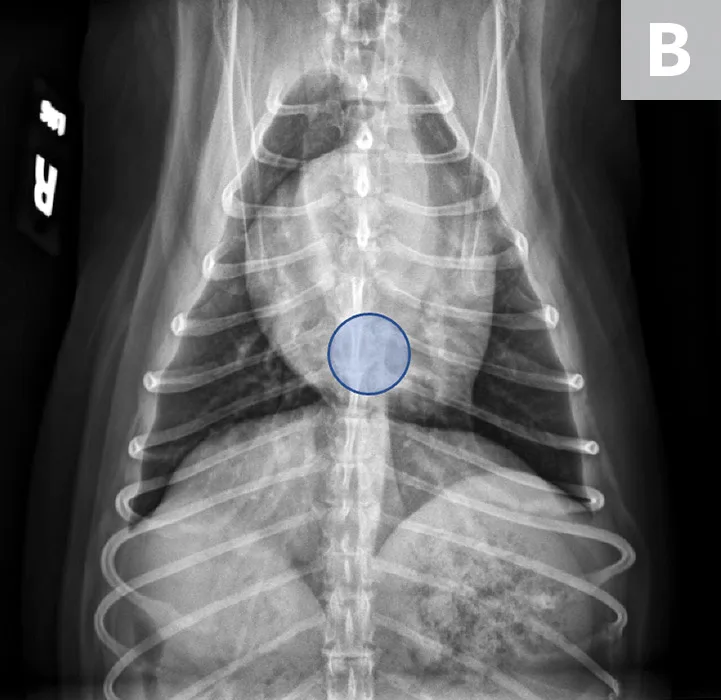

FIGURE 2

VLAS measurement in a dog with suspected stage B2 MMVD using a right lateral radiograph (A). A caliper was used to measure from the center of the most ventral aspect of the carina to the most caudal aspect of the left atrium, where it intersects with the dorsal border of the caudal vena cava. This measurement was transferred to the cranial aspect of T4 and extended caudally along the thoracic vertebrae. The number of vertebrae this line transversed was rounded to the nearest tenth to determine VLAS (2.8 VBUs). Stage B2 MMVD was confirmed via echocardiography. Other structures are unremarkable. An orthogonal radiograph of the patient provides a more complete evaluation of cardiac silhouette (B); normal location of the left atrium is indicated (circle).